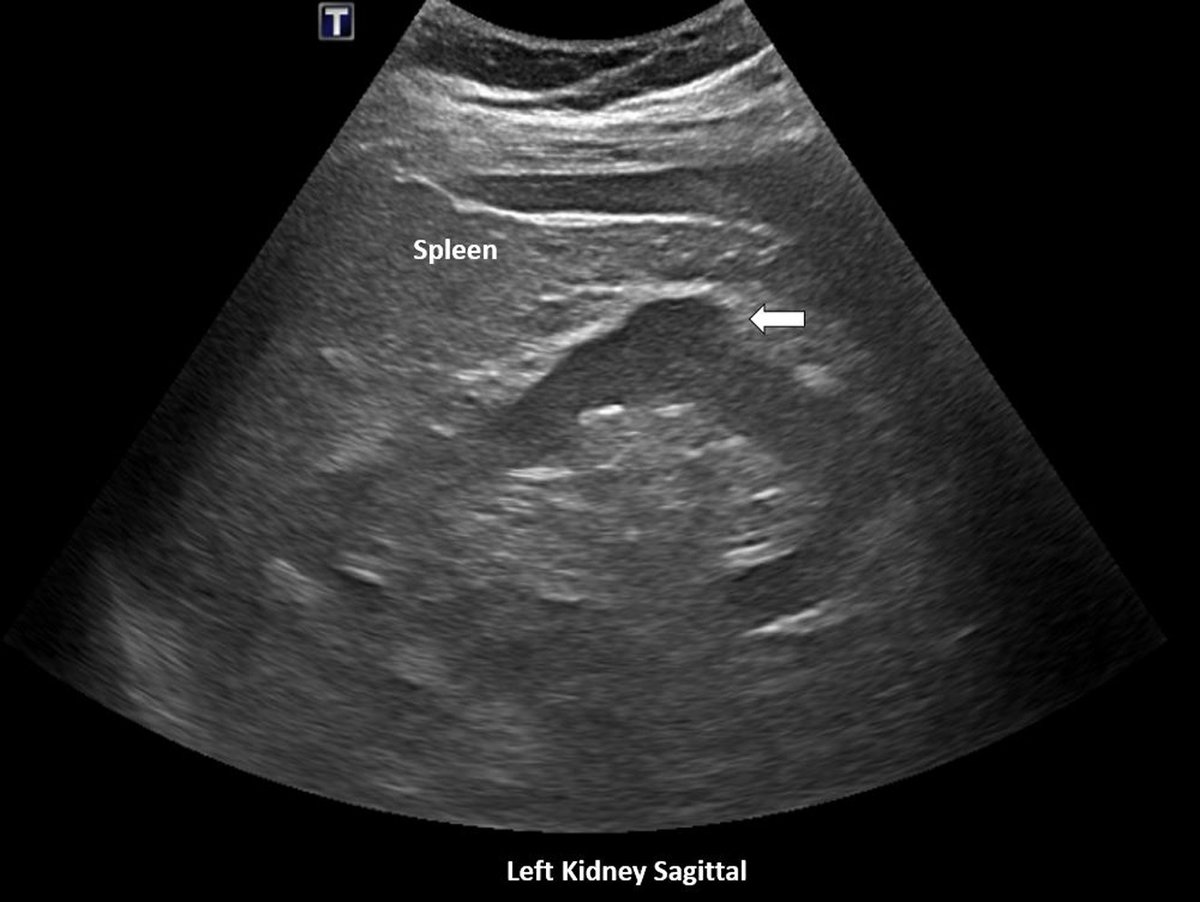

A 58-year-old man with a history of hypertension, obstructive sleep apnea, and mildly elevated serum creatinine

👉underwent renal ultrasonography for evaluation of kidney size and structure

The scan reported no structural abnormalities except for a “protuberance” in the left kidney

👉 reassured that this was a benign finding called “dromedary hump”

Dromedary hump is a prominent focal bulge on the lateral border of the left kidney caused by splenic impression, which can mimic renal neoplasm.

The hump demonstrates the same echogenicity as adjacent normal renal parenchyma on the sonogram

👉unlike renal cell carcinoma, which typically appears as a heterogeneous mass with areas of necrosis, cystic changes, and hemorrhage